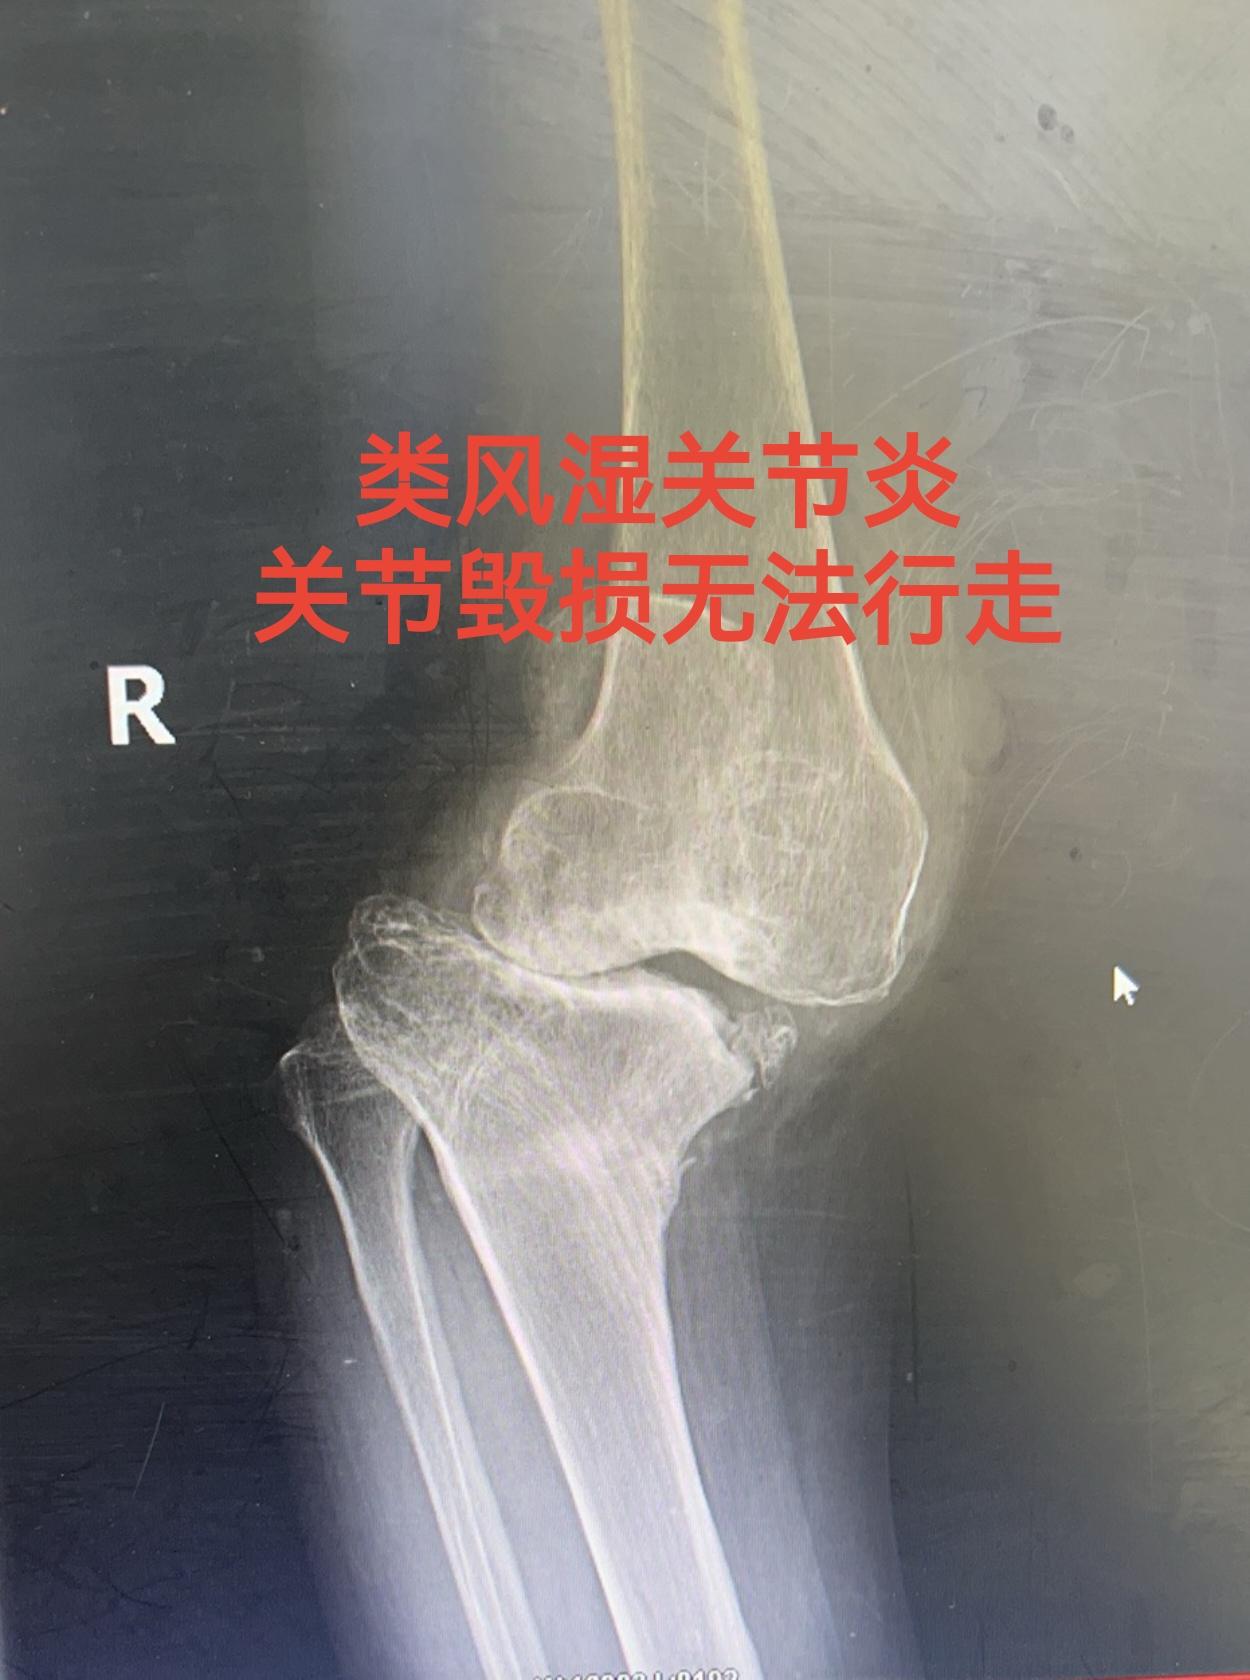

类风湿关节炎。类风湿关节炎,关节毁损,无法行走。备的CCK和铰链膝,最...